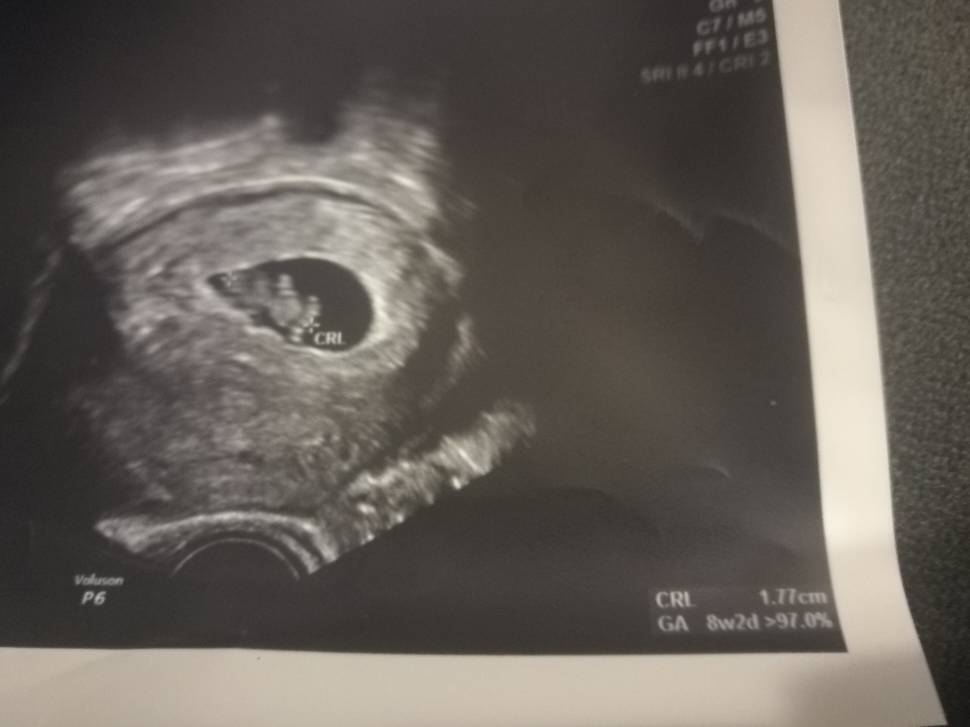

Wszystko w porządku. Serduszko bije, dzieciątko widziałam i w sumie tyle. Nwm jak u Was wyglądała pierwsza wizyta (liczę pierwsza bo jest serduszko) ale ja chyba trochę rozczarowana jestem. Dostałam spis badań które mam zrobić prywatnie, lekarz w tej przychodni gdzie ja chodzę bd dopiero 7 stycznia i mówi do mnie ze dobrze żeby mnie wcześniej zobaczył. Mówił więc żebym probowala się dostać do drugiej przychodni gdzie przyjmuje na 21.12. A jeśli się nie uda to może do jakiegoś innego lekarza żeby mnie zobaczyl za dwa tyg. Karty ciąży nie założył, terminu nie wyliczył, żadnego ważenia mierzenia ciśnienia. Nwm też tak jak pisalam jak to wygląda w Pl na początku bo poprzednio prowadziłam ciąże we Fr.

Też tak miałam na pierwszej wizycie gdzie bylo serduszko. Dostalam tylko skierowanie na badania krwi i moczu. Powiwdziala ze jest wszystko ok i ze karte ciazy zalozymy na nastepnej wizycie jak bede miala wyniki krwi. Zadnego mierzenia wazenia cisnienia....zobaczymy jak bedzie teraz :)